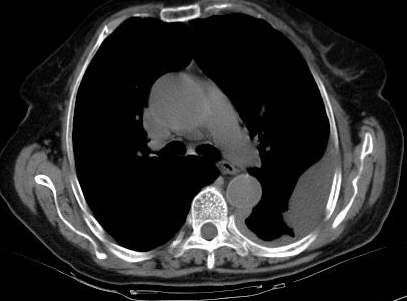

请上传纵隔窗。目前还是支技包裹性积液(明显梭形),即使是间皮瘤并积液也少梭形的。

标题: 回复:病历讨论,胸膜间皮瘤?(是同一个病人吧)

从图片看,包裹性积液好象更合理,梭形,ct值3-5hu(在哪看到的?);胸膜间皮瘤如此规则,不多见。

左侧背部胸膜肥厚,伴包裹性积液,不考虑间皮瘤.

同意以上各位的高见,首先考虑包裹性积液,1.胸膜间皮瘤积液量一般较大,以游离性积液更为常见,2.可以看到增厚的胸膜结节